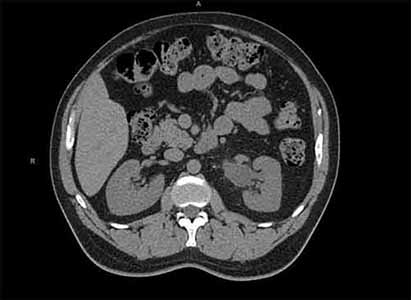

Left-sided Abdominal Pain in a 45-yr-old Man

Test Result 2

CT scans without contrast of the abdomen and pelvis are obtained and are shown.

Select each image to review.